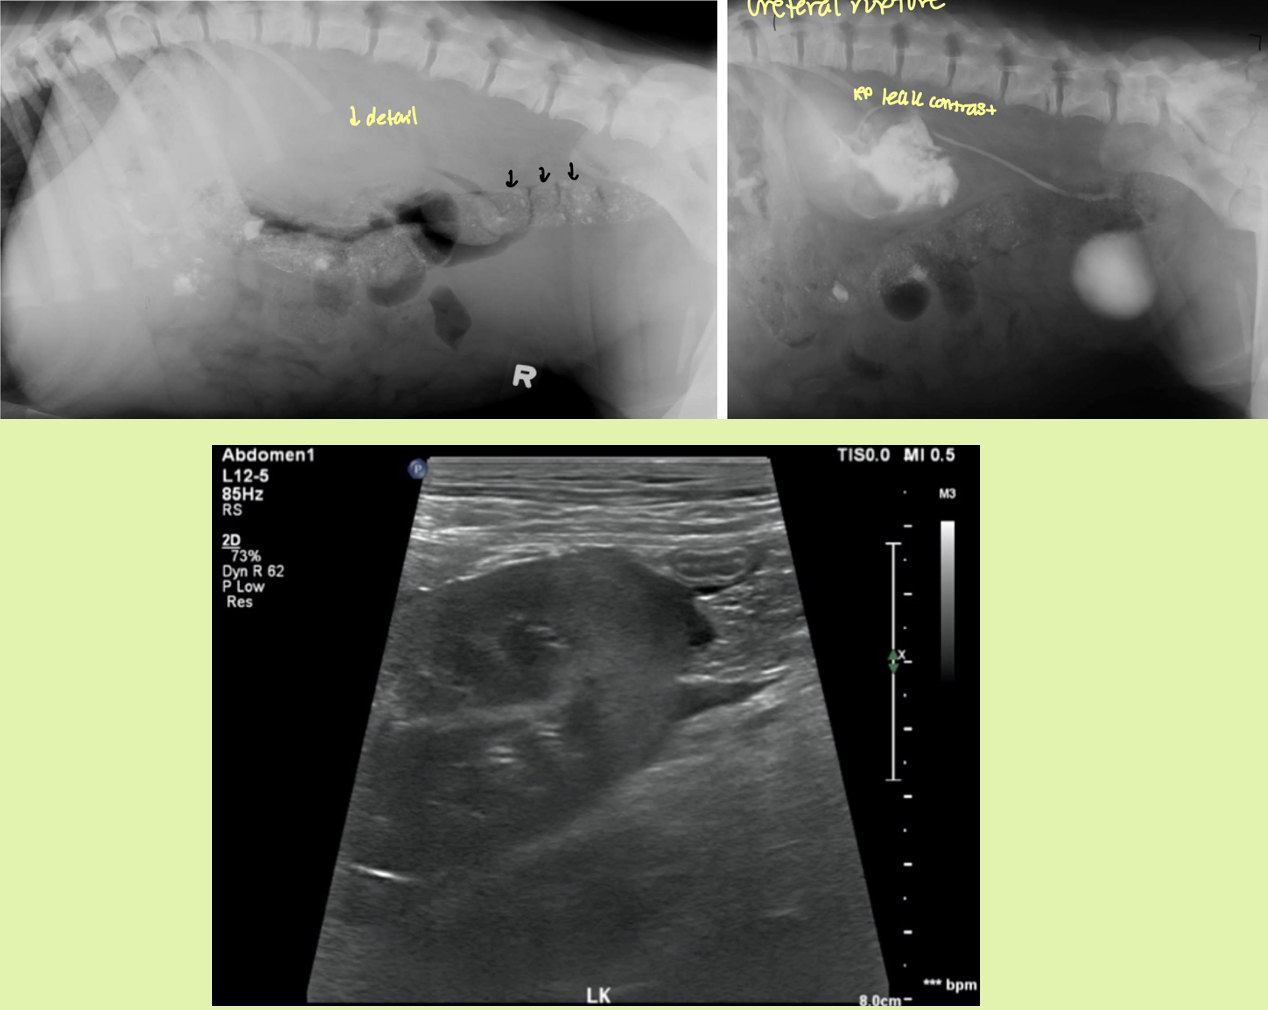

preferred method to ID ureteral rupture

EU/IVP

dog with trauma hx has decreased RP detail and leakage of contrast material into both the peritoneal and RP space

ruptured ureter

avulsion — peritoneal space

rupture — RP space

how would you be able to differentiate a ruptured kidney vs ureter

kidney rupture - injured kidney with opacify inhomogenous

ureter rupture -only one ureter will light up with contrast and deposit into bladder